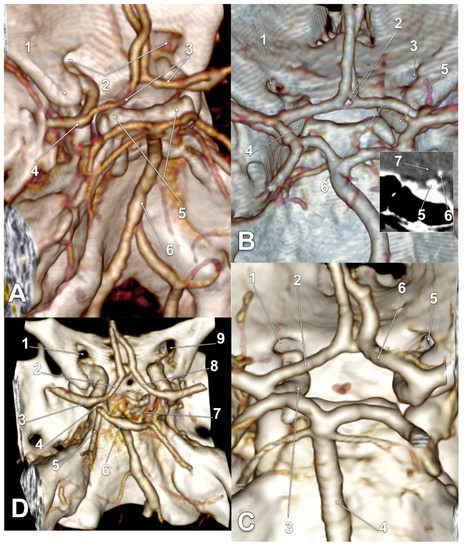

| M | type 3 IO A1 SCar | type 3 IO A1 SCar | high BA bifurcation | Figure 3A |

| M | type 3 IO A1 | type 3 IO A1 | Figure 2D | |

| M | type 2 IO A1 | type 1 IO A1 SCar | fenestrated AComA, hypoplastic left A1 | Figure 2A |

| M | type 2 IO A1 | type 2 IO A1 SCar | Figure 4C | |

| M | type 2 IO A1 | type 2 IO A1 | Figure 4A | |

| M | type 2 IO A1 | type 2 IO A1 | Figure 5B | |

| F | type 2 IO A1 | type 2 IO A1 | rotated BA, left PCA displaced towards the ipsilateral A1 ACA | Figure 4D |

| F | type 2 IO A1 | type 2 IO A1 | duplicated AComA | Figure 4B |

| F | type 2 IO A1 SCar SClin | type 1 IO A1 | supraclinoid right A1 | Figure 2C |

| F | type 2 IO A1 | type 2 IO A1 | Figure 3D | |

| F | type 2 IO A1 | type 2 IO A1 | Figure 3B,C | |

| F | type 2 IO A1 SCar | type 2 IO A1 SCar | rotated AComA, hypoplastic right A1 | Figure 5A |

| F | type 2 IO A1 | type 2 IO A1 | rotated BA, left PCA displaced towards the ipsilateral A1 ACA | Figure 5C |

| F | type 1 IO A1 | type 2 IO A1 | left bihemispheric ACA | Figure 2B |